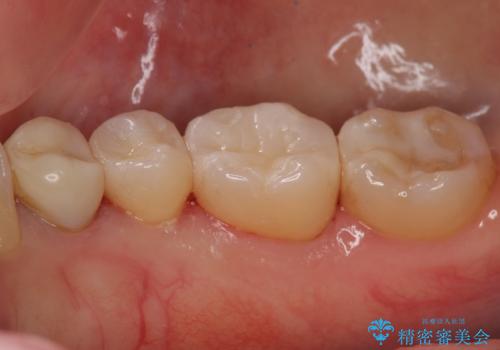

拡大鏡下で詰め物を外し、う蝕がない事を確認して、セラミック(e-maxインレー)で治療を行いました。

セラミックの詰め物(e-maxインレー)は歯質との隙間ができにくく

虫歯の再発リスクが低くなります。

口を開けた時、銀歯が目立たなくなり、大変満足して頂けました。